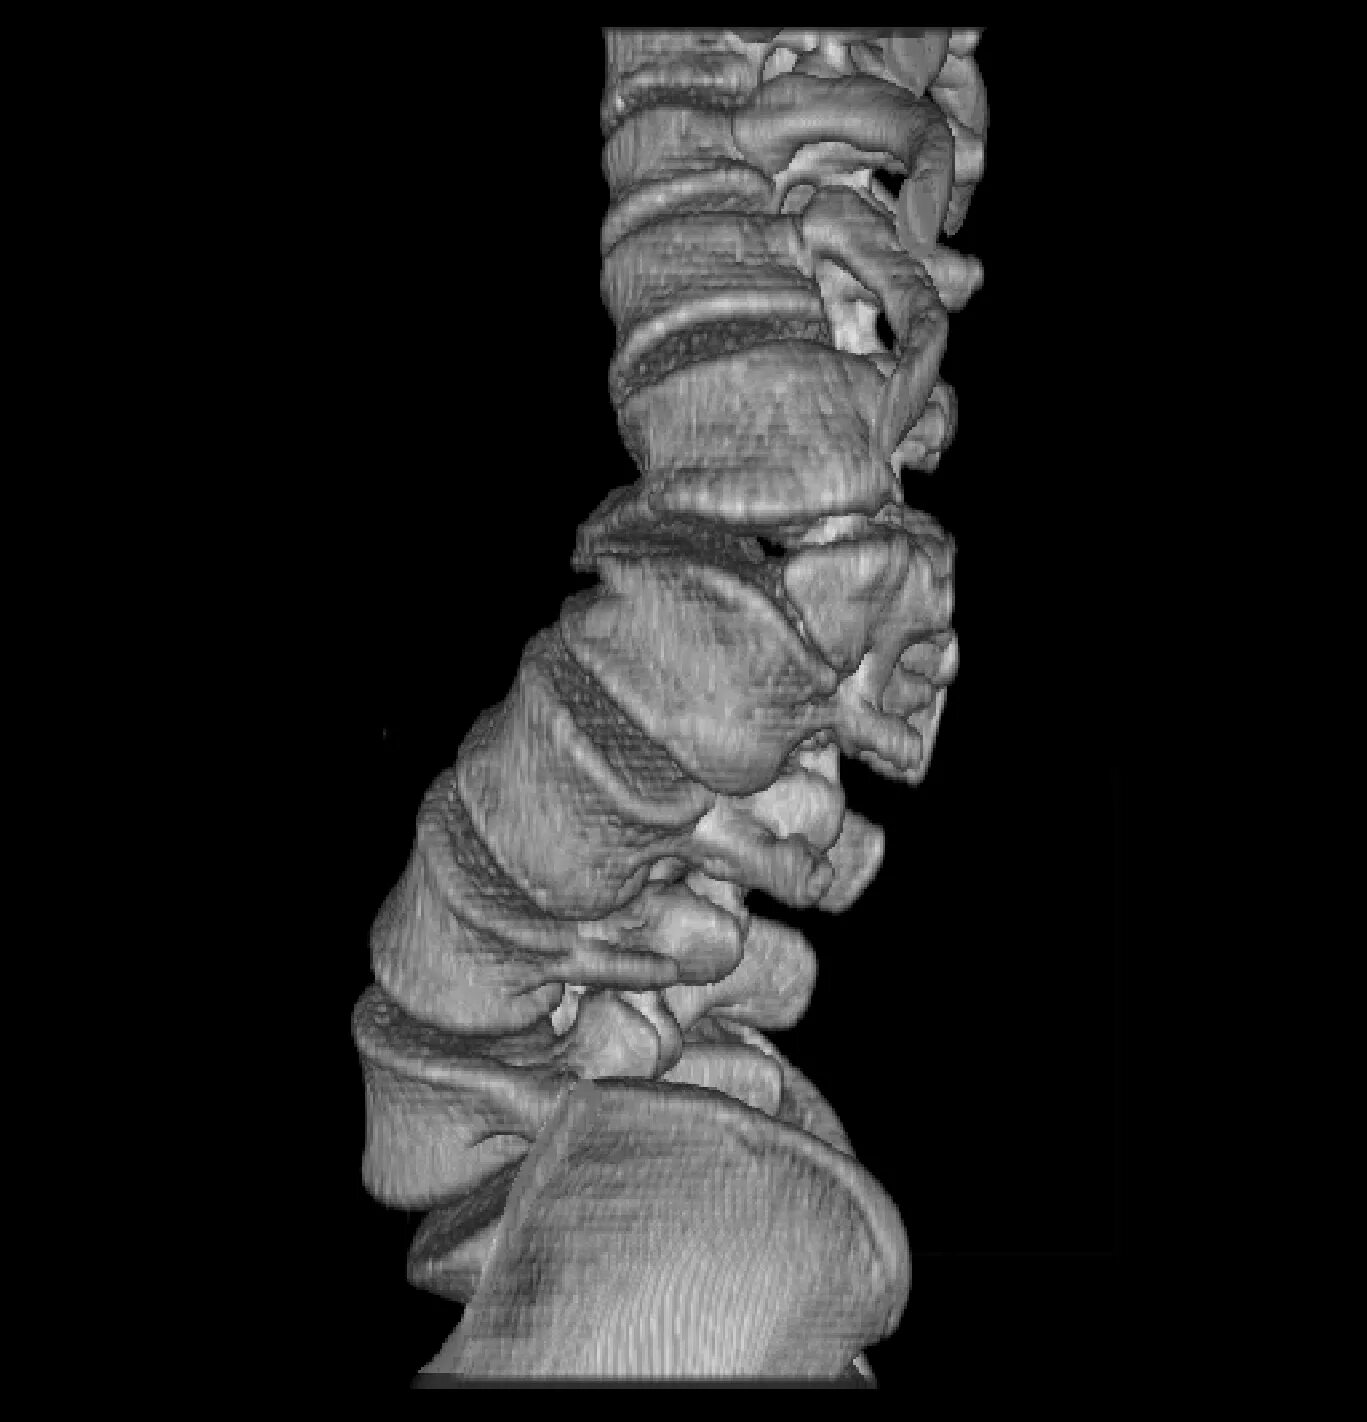

Анатомические и функциональные аномалии